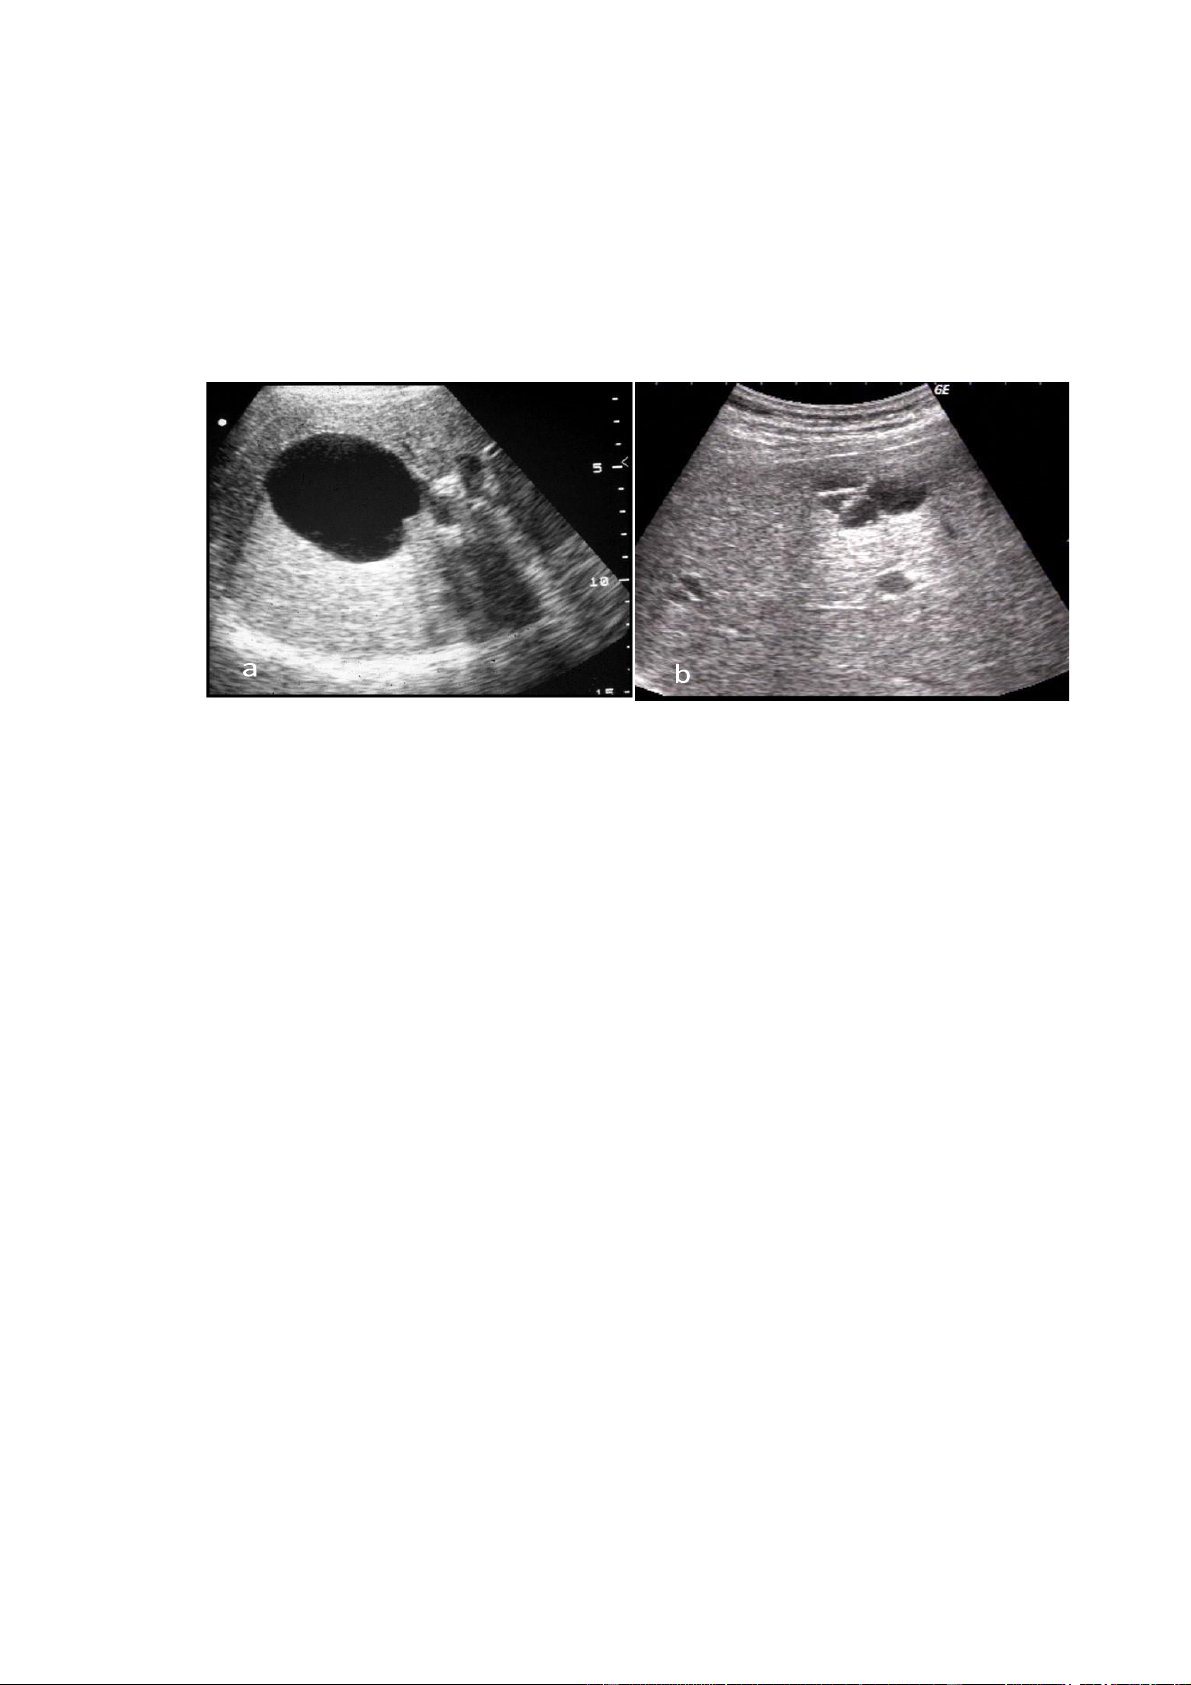

3. CÁC KHỐI U GAN LÀNH TÍNH 3.1.Nang gan

Chẩn đoán xác định

Nang gan biểu hiện bằng vùng rỗng âm tròn hoặc bầu dục với hình tăng âm

phía sau. Thành nang mảnh và rõ nét. Nhu mô gan xung quanh nang hoàn toàn bình thường.

Thường có một hoặc hai nang. Trong trường hợp nhiều nang thì hình ảnh

siêu âm của mỗi nang không thay đổi. Một số các trường hợp gan đa nang thường

kèm theo thận đa nang gọi là bệnh gan-thận đa nang, đôi khi kèm theo tụy đa nang.

Bệnh gan-thận đa nang thường có tính chất gia đình.

Hình.3.1. a. Nang gan điền hình không có vách với hình rỗng âm và tăng âm phía

sau; b. Nang gan có vách ngăn. 3.2.U máu gan